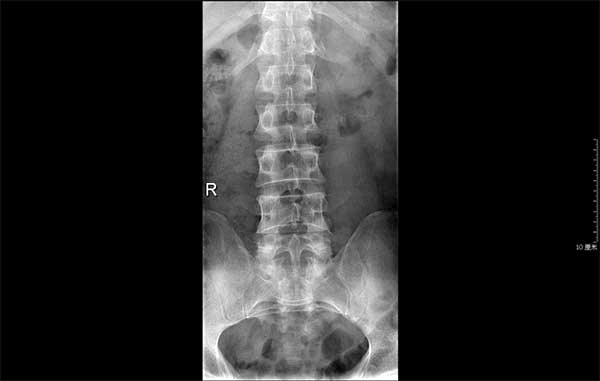

X光片显示叶先生的髂嵴高,腰5横突过长

在叶先生的腰椎核磁共振及X光片上发现,患者的腰椎间盘突出节段是在第五腰椎和骶椎间的椎间盘(即腰5骶1处)。但由于患者的第五腰椎横突较长,如采用椎间孔入路椎间孔镜的手术方式,会给穿刺和手术过程带来困难,也会增加患者的痛苦。医生介绍,就像一个打钻机,在打墙时遇到了坚硬的阻碍物,钻头便无从下手。既要保证手术的质量,又不增加患者的创伤和痛苦,主诊的肖丹副主任医师给出了解决难题的办法:改变入路口,采用椎板间入路椎间孔镜下髓核摘除的手术方式,以避开椎间孔入路带来的困难,又能保持微创的特点。